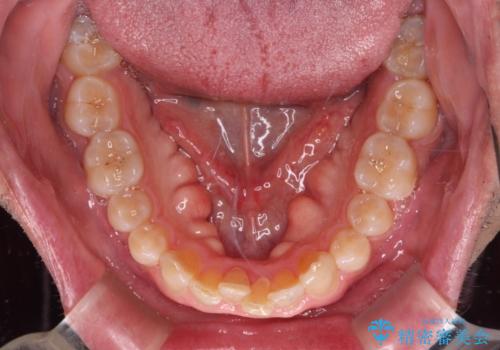

- 前歯のデコボコを気にして来院された患者様です。

インビザラインでもワイヤー装置でも対応可能でしたが、仕事の都合で来院回数を減らしたいとのことでインビザラインによる矯正治療を選択されました。

著しく咬合力が強いため、奥歯がしっかりと噛めずに治療が長引くことが懸念されました。

1セット目のインビザラインを使用した際には左右ともに大臼歯が咬み合っていなかったのですが、2セット目できっちりと仕上げることができました。